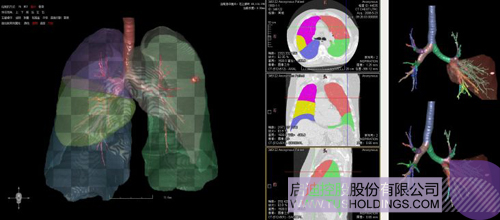

数字肺——肺结节手术规划系统

完整的三维影像智能分析技术;

完整的三维可视化以及相关建模、几何分析技术;